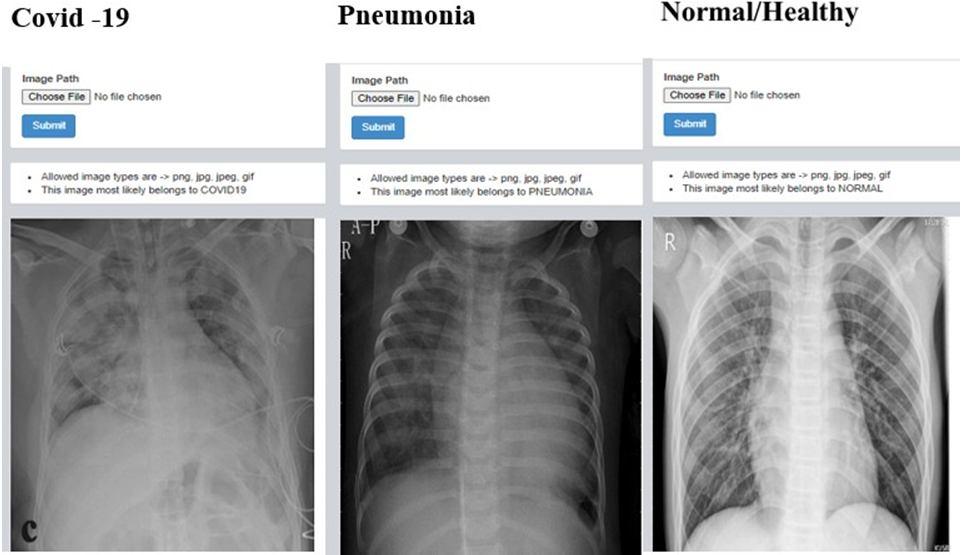

G. Results of web application

1) Detection of Covid 19 , Pnuemonia and Healthy chest x ray: Here the X ray images are fed by clicking on choose file in dash board after that we need to select file in which the images are present and upload it once after uploading needto click on submit button once after the submiting image we can observe result whether the given X ray belong to covidor pneumonia or normal.The same procedure is followed for many iteration to check whether develop web application is accurate by feeding different types of X ray images.

Fig. 23: Iteration 7

CNN that has been trained using these improved images. CNNhas a classification accuracy of 100% for X Ray pictures and photos when it is trained with these improved images. The experimental outcomes were deemed to be quite convincing, and they were helpful for COVID 19 screening on chest X rayimages of individuals who potentially have a corona.